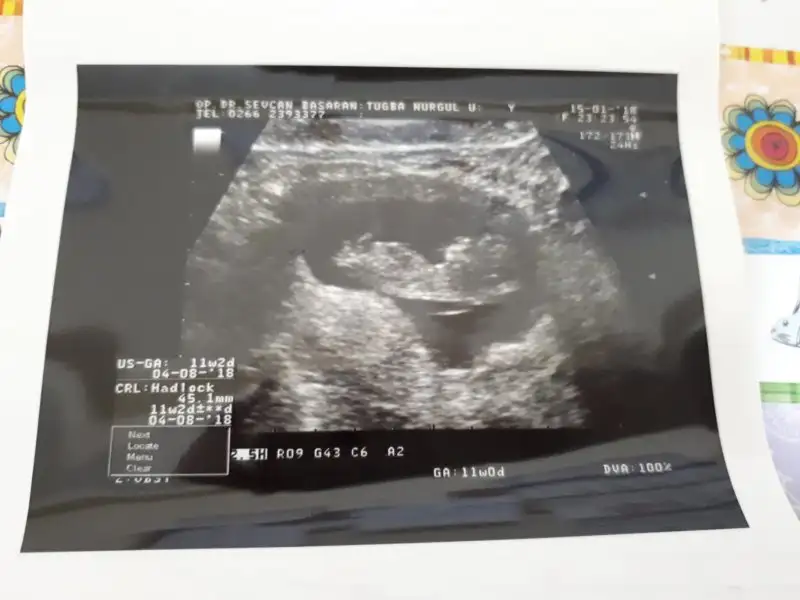

Pazartesi gideceğim atarım canım 9 haftalıkken ki resmi var hayırlısıyla ilk dönem biterse rahat edeyim birazcıkİlk trimester bitiyor bile, ikinci trimester en güzeli, üç giderek zorlaşıyor :) yok mu bu haftalarda ultrason resmi, tahmin yürütürüz :)

Çok merak ediyorum cinsiyetini pazartesi atarım gene canımBu resimlere bayılıyorum, ne çok beklemedik biz bu sıpaları görebilmek için. Haftaya gittiğinde atarsan daha net söyleriz ama şu resme göre kıza benzettim :)

Oyyy nasılda büyümüş bu minnos ben hic anlamiyorim cinsiyetten ama

Büyüdük teyzesi Allaha şükür :) doktorumuzda göremedi cinsiyeti bakalım haftaya 2li tarama var görür belki :) çoğunluk erkek diyorMinik nokta büyümüş de kuzu olmuş :) yerim ben onu. Bu haftalarda tam minyatür bebekler :) maşallah

Canım nub u net belli olmuyor ama erkeğe benziyor kemik yapısı bu fotoğrafta.